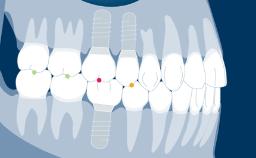

Ao fornecer a um paciente uma reabilitação sobre implante, os clínicos devem decidir se fabricam uma prótese provisória ou se vão diretamente para a prótese definitiva. Vários fatores desempenham um papel na tomada da decisão correta. Estes envolvem a localização do implante em região anterior ou posterior, o número de implantes, a necessidade de moldar o tecido, como é frequentemente visto com implantes adjacentes à região anterior, e a necessidade de suporte oclusal. Os desejos do paciente também podem desempenhar um papel nesta decisão. Este módulo irá destacar as indicações, materiais e técnicas para a fabricação e utilização de uma prótese provisória implantossuportada.